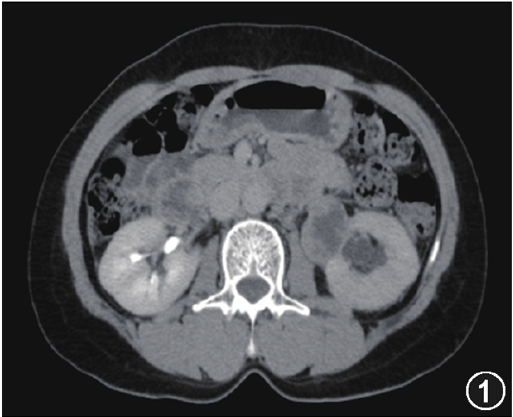

查体:双肾区无叩痛,双侧输尿管走行区及膀胱区无压痛、未及明显包块,膀胱不充盈。增强CT检查

:左侧输尿管上段见一类圆形等低混杂密度肿块,大小约3.6 cm×2.8 cm,边界较清,增强扫描示病灶实性成分不均匀强化(图1),左肾动脉、静脉被包绕,边界不清,左侧输尿管上段及左肾盂扩张积水,左肾强化减弱;肾周脂肪间隙密度未见增高;盆腔内未见肿大淋巴结,少量盆腔积液;印象为左输尿管上段肿块,首先考虑恶性肿瘤伴左肾积水,累及左肾动脉、静脉,少量盆腔积液。术前诊断为左输尿管肿物(恶性肿瘤)。

图1.增强CT检查示左输尿管上段一类圆形等低混杂密度肿块,大小约3.6 cm×2.8 cm,边界较清,病灶实性成分不均匀强化